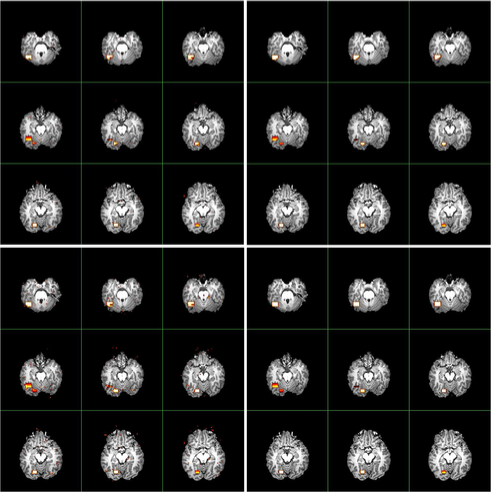

The data are generated from a semi-parametric model similar to that in Section 5.2 of Zhang and Yu (2008). (They demonstrated that the semi-parametric model gains more flexibilities than existing parametric models.) The left panel of Figure 6 contains slices (corresponding to the 2D axial view) which highlight two activated brain regions involving activated brain voxels. The neighborhood used in the procedure is illustrated in the right panel of Figure 6.

Figure 7 compares the activated brain regions identified by the (in the left panels) and (in the right panels) procedures. Owing to the wealth of data, and for purposes of computational simplicity, results using Method I of are presented. Voxel-wise inactivity is tested with the semi-parametric test statistics (in the top panels) and (in the bottom panels) whose notation was given and asymptotic distributions were derived in Zhang and Yu (2008). The control level is . Inspection of Figure 7 reveals that and locate both active regions. In particular, using the procedure, both methods detect more than voxels (which are visible when zooming the images), many of which are falsely discovered. When applying the procedure, detects voxels, whereas detects voxels. Thus the procedure reduces the number of tiny scattered false findings, gaining more accurate detections than the procedure.

As a comparison, the detection results by popular software AFNI [Cox (1996)] and FSL [Smith et al. (2004) and Woolrich et al. (2001)] are given in Figure 8. We observe that both AFNI and FSL fail to locate one activated brain area, and that the other region, though correctly detected, has appreciably reduced size relative to the actual size. This detection bias is due to the stringent assumptions underlying AFNI and FSL in modeling fMRI data: the Hemodynamic Response Function (HRF) in FSL is specified as the difference of two gamma functions, and the drift term in AFNI is specified as a quadratic polynomial. As anticipated, applying the distributions restricted to parametric models to specify the distributions of test statistics in AFNI and FSL leads to bias, which in turn gives biased calculations of -values and -values. In this case, the detection performances of both the and procedures deteriorate, and the procedure does not improve the performance of the procedure. See Table 3 for a more detailed comparison.